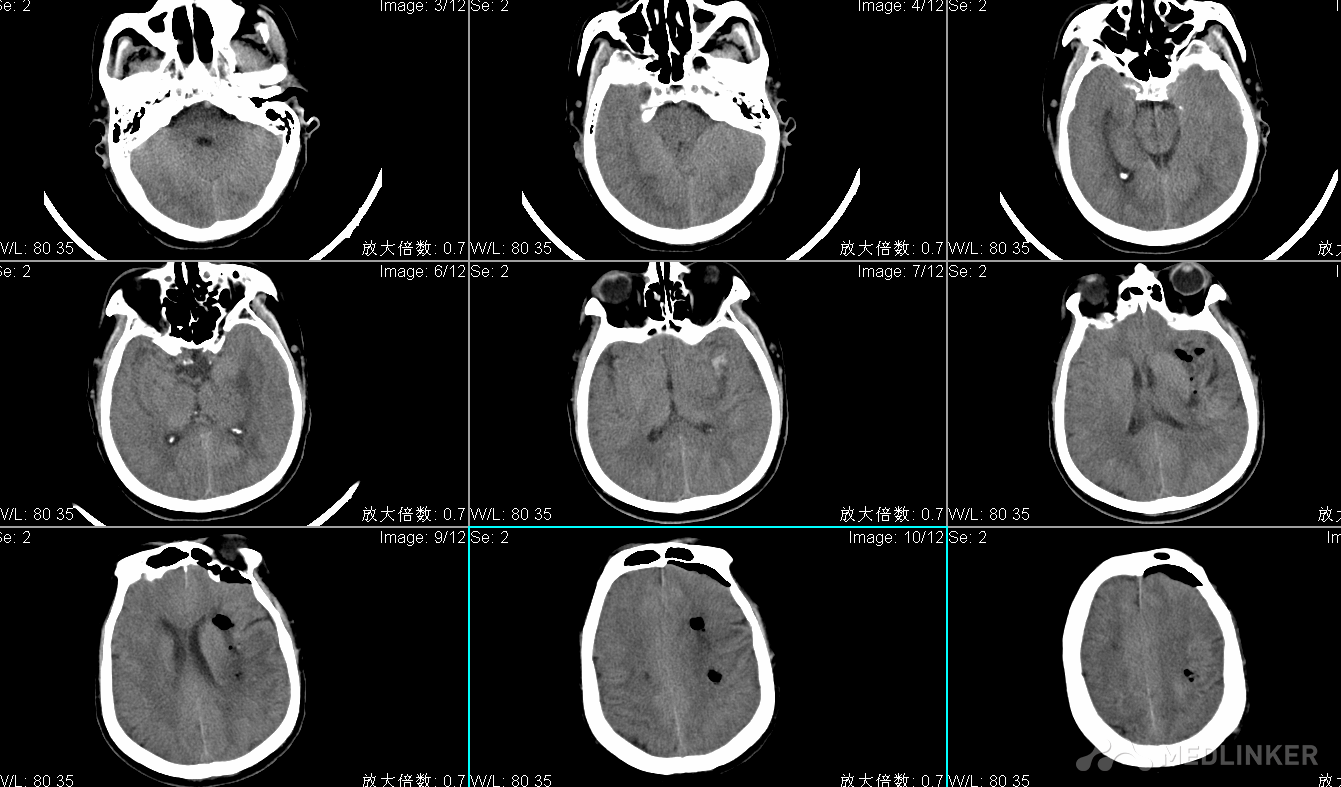

查体:T:36℃ P:83次/分R:23次/分BP:181/118mmHg,昏睡,刺痛可睁眼,可发音,四肢刺痛屈曲,双侧瞳孔直径左:右=3:3mm,光反射灵敏,右侧鼻唇沟变浅,四肢肌力检查不合作,肌张力不高,腱反射(++),生理反射存在,右侧巴氏征(+); 头CT检查显示左侧基底节区脑出血多田公式计算出血量约80ml;

头CT显示左侧基底节区脑出血约80ml

术后CT显示左侧基底节区脑出血清除良好。 高清手术视频 总结: 1.该手术实施前首先排除患者颅内动脉瘤破裂导致的颅内出血,若血肿位于外侧裂附近伴蛛网膜下腔出血的患者,先行头CTA检查,以排除颅内动脉瘤,若为动脉瘤性脑出血采取开颅颅内动脉瘤夹闭术; 2.神经内镜辅助脑出血清除术适合脑疝前期及早期的患者,若患者脑疝形成时间较长,以及弥漫性脑肿胀的患者,因神经内镜微创手术起不到减压的作用,我们应采取开颅血肿清除术+去骨瓣减压术; 3.神经内镜辅助脑出血清除术的难点是止血,因为该手术微创,操作空间比较小,因此我们采用长头双极或电凝吸引器止血的方法; 4.神经内镜辅助脑出血清除术的要点是定位与路径选择,术前要规划好; 5.由于自发性脑出血与颅脑外伤不同,一般情况下血肿清除后,脑组织塌陷明显,不需要去骨瓣减压,若术中出现弥漫性脑肿胀,额部纵行切口后延行额颞开颅去骨瓣减压术; 6.术后硬脑膜严密缝合,若有缺损,可采用预留的骨膜修补硬脑膜。 7.神经内镜辅助脑出血清除术一般手术时长约1.5小时,而常规开颅手术时间约3-4小时,神经内镜手术时间明显缩短,手术创伤小,恢复快,颅内感染风险大大降低,术后短时间可转普通病房,住院费用降低,且避免二次颅骨修补术,值得大力推广。